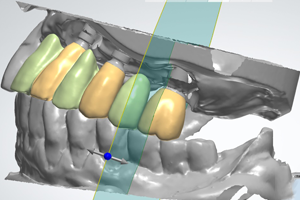

Dankzij de opkomst van CAD/CAM tandtechniek kan de tandarts bij het ontwerpen van occlusie en articulatie ook bij indirecte technieken aan het roer blijven staan.

Tijdens deze lezing komen de volgende aspecten aan de orde: Esthetische en functionele analyse, behandelplanning, teamwork, materiaalselectie, CAD/CAM techniek, digitale beetbepaling, 3D gezichtsscan, moderne hoog-gevulde polymeren en volkeramiek.